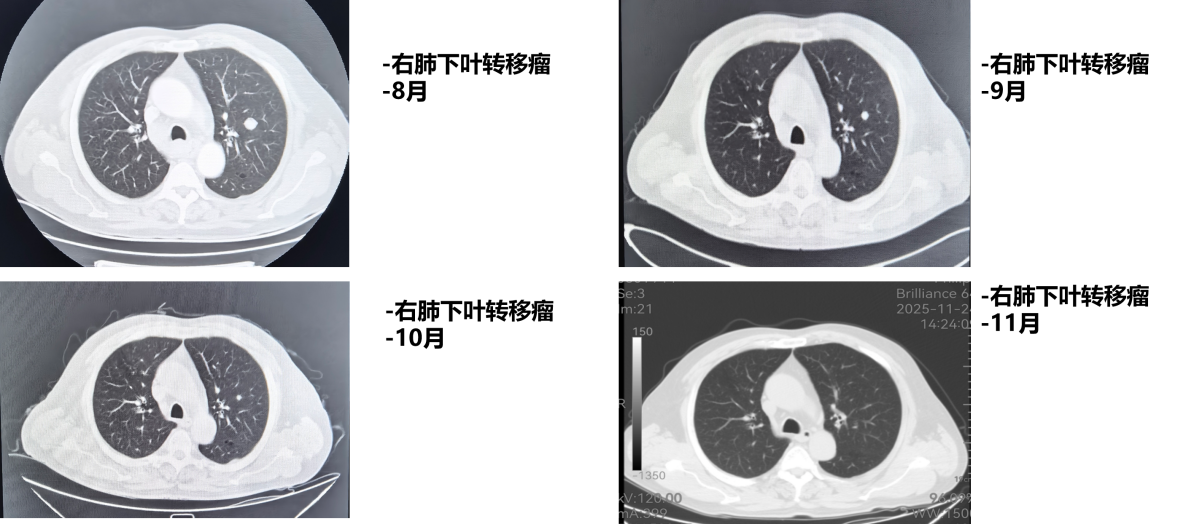

1周期后(2025年9月)复查CT:食管病变、纵隔淋巴结较前减小,双肺转移结节较前部分减小。1周期即显现疗效。

4周期后(2025年11月)复查CT:与2025-10-17日图像对比,食管癌治疗后改变,同前相仿;纵隔淋巴结治疗后改变,较前减小;双肺多发小结节,考虑转移瘤治疗后改变,部分较前略减小。

疗效评估:达到部分缓解(PR)

本例患者PD-L1 CPS评分为3分,属于CheckMate 648研究中获益更为显著的PD-L1阳性人群。经过4个周期纳武利尤单抗联合化疗后,影像学复查显示原发灶及所有转移病灶均明显缩小,疗效评估达PR,与研究中PD-L1阳性患者高达53%的ORR相符。